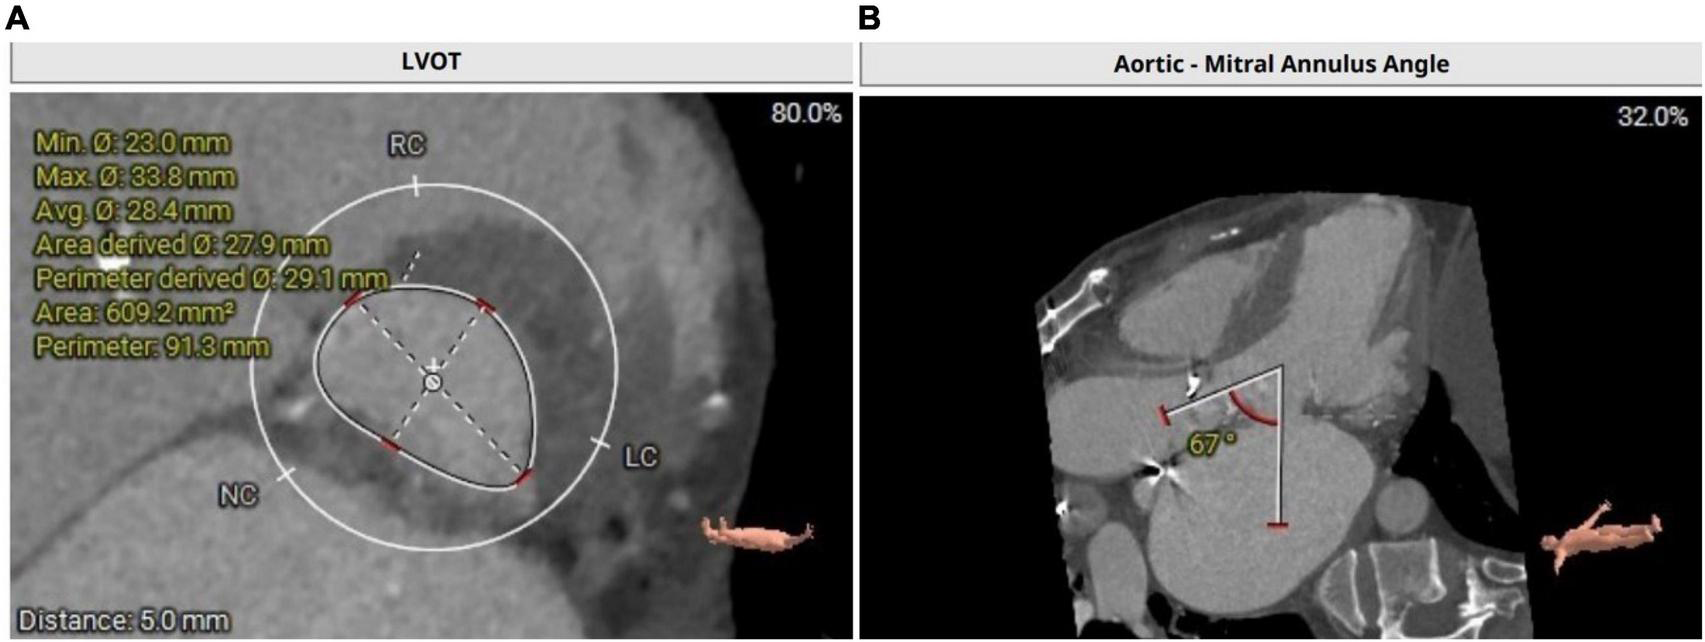

Transthoracic echocardiography revealed moderate bioprosthetic mitral valve stenosis (valvular orifice area of 1.8 cm2) with severe mitral valve regurgitation (regurgitant area of 16.2 cm2) and concurrent severe bioprosthetic aortic valve regurgitation, severe tricuspid regurgitation (regurgitant area of 18.8 cm2). Furthermore, the left ventricular end-diastolic diameter was 63 mm with a normal ejection fraction of 58%. Computed tomography angiography of the coronary artery showed a 50–60% stenosis in the middle segment of the anterior descending artery. The left ventricular outflow tract was calculated with 609 mm2 (Figure 1A). Aorto-mitral angle was steep with 67° (Figure 1B). Left coronary ostium height is 12.8 mm, right coronary ostium height is 14.3 mm. The frailty screening scale was four points. The preoperative logistic EuroSCORE II for redo surgery in this patient was calculated with 19.02%. Considering preoperative EuroSCORE II, the redo surgery and the extensive experience with transapical transcatheter aortic valve replacement (TAVR) procedures at our institution, the decision was made to perform a simultaneous transapical VIV procedure in the mitral and aortic positions.

FIGURE 1

(A) Calculation of left ventricular outflow tract with an area of 609.2 mm2. (B) CT depicting a steep aorto-mitral annulus angle with 67°.